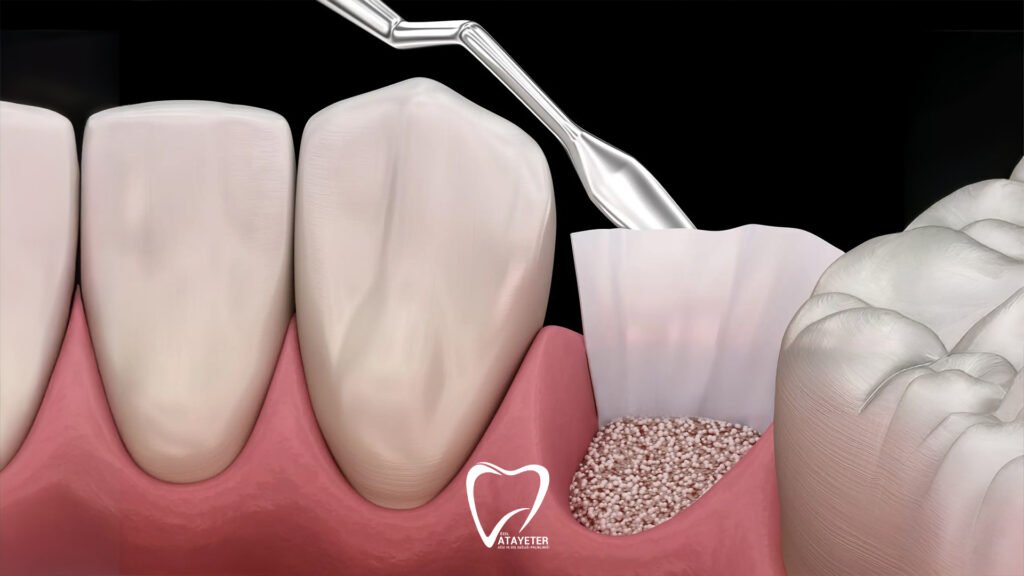

After the preparation is complete, a special bone graft material is placed into the area where bone loss exists. These materials can come from different sources. In some cases, the patient’s own bone may be used, while in other situations human derived, animal derived, or synthetic bone materials produced in laboratories may be preferred. Today, most graft materials used in dentistry are specially designed to be safe and fully compatible with the human body. Once placed, they act as a framework that supports the growth of new bone tissue.

The grafted area is often covered with a thin protective membrane after the material is placed. This membrane helps protect the graft and supports a healthier healing process. It also encourages the new bone tissue to develop in a more organized way. Finally, the area is closed with small stitches, and the healing process begins.